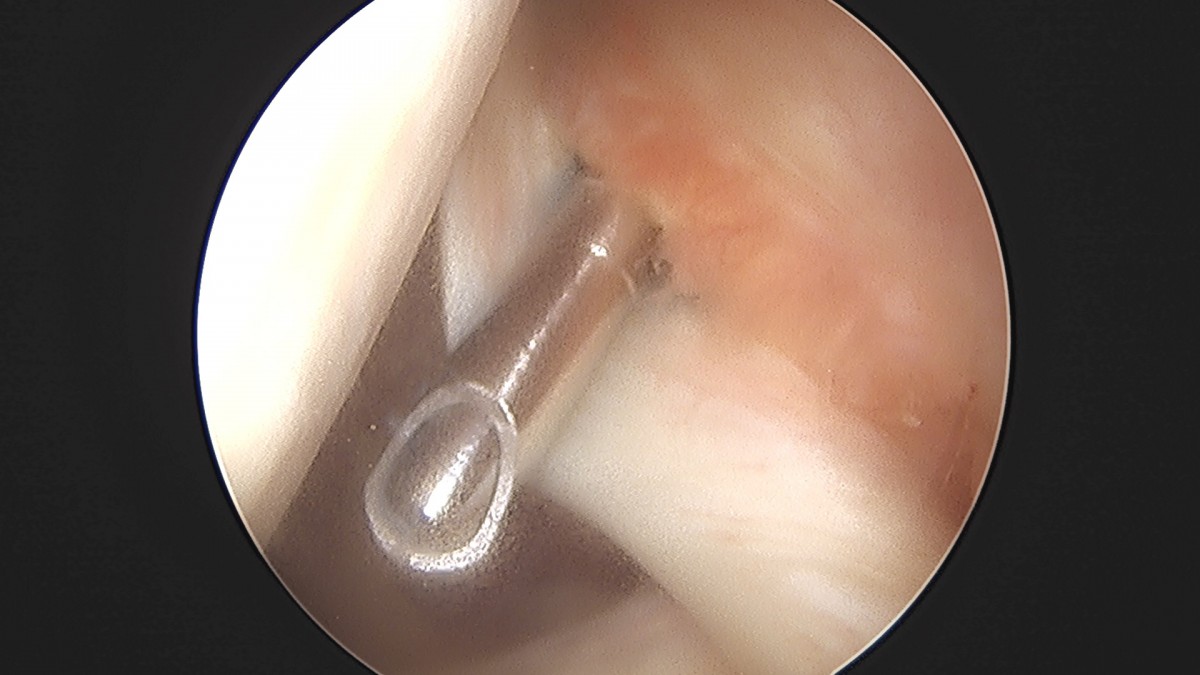

이재상원장님 어깨 견봉하 감압술 및 관절낭 이완술 양명O 환자

작성자 최고관리자 댓글 0건 조회 788회 작성일 25-09-16 15:33